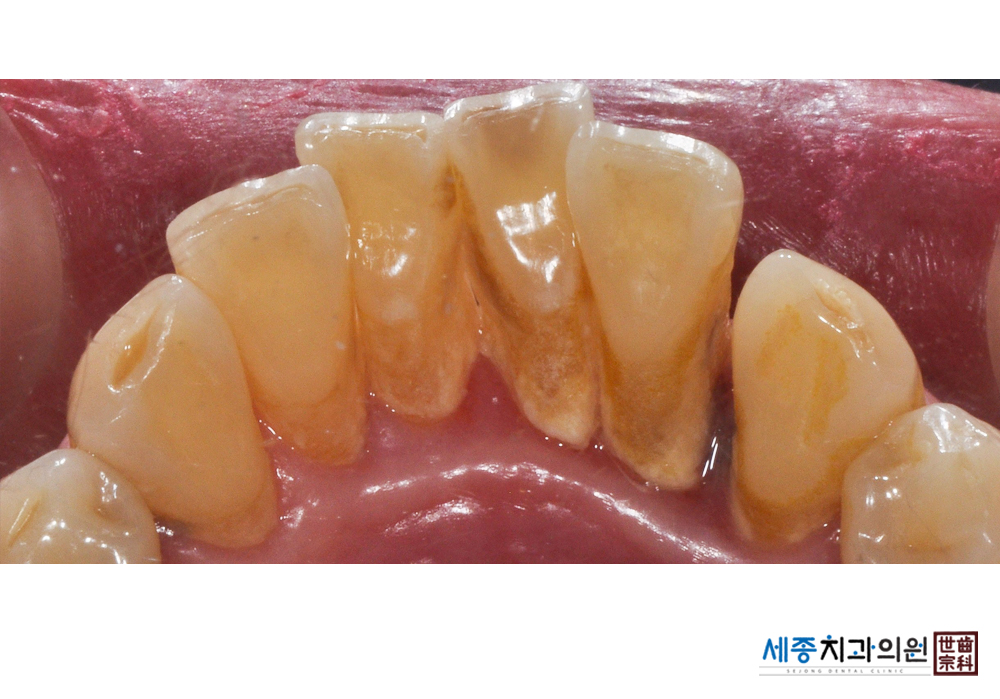

[스케일링] 치주질환 예방 스케일링 치료

치료전 : 2019-03-29

가글마취&저주파 스켈러를 사용한 스케일링